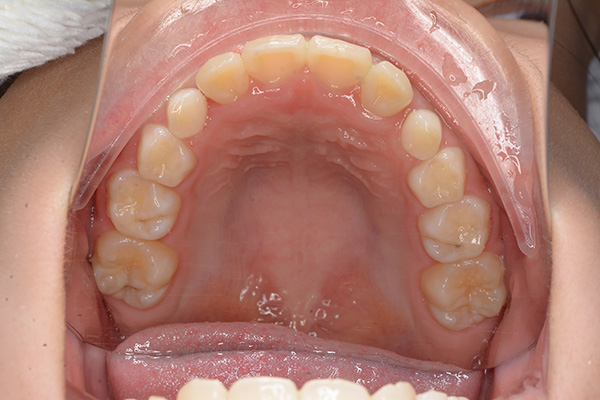

動的治療開始前(9歳7ヵ月)

動的治療開始前

(9歳7ヵ月)

IOP